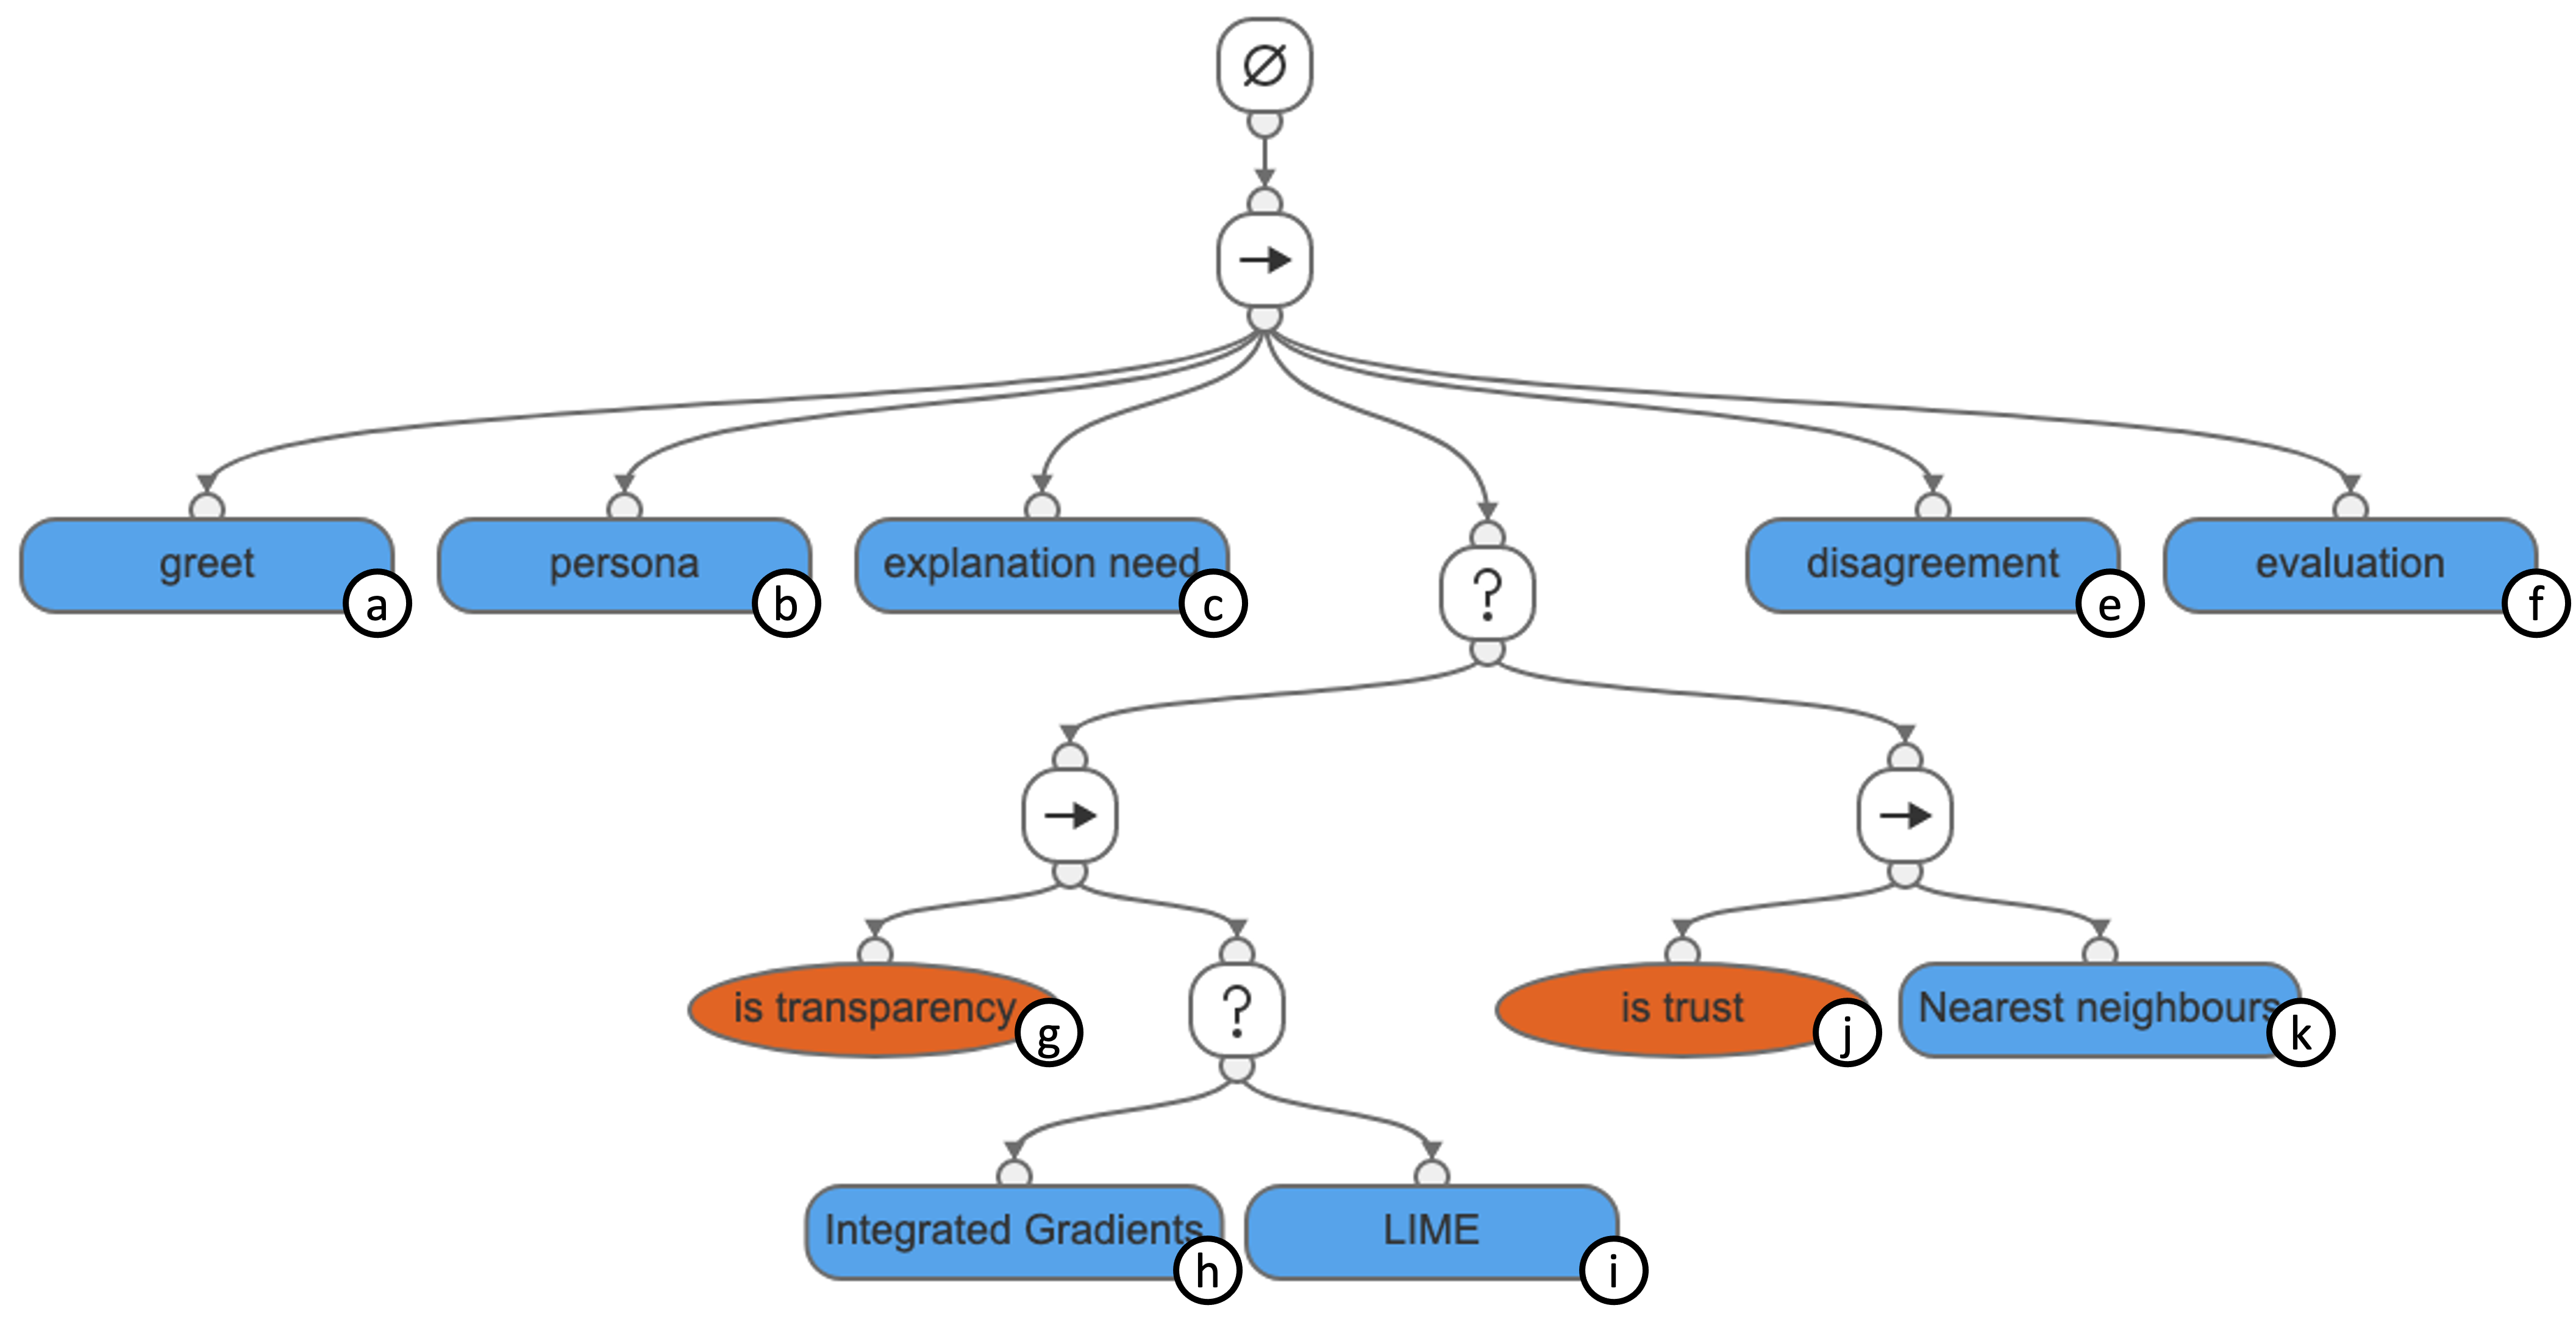

| Explainers | Feature attribution using Integrated Gradients and LIME to satisfy transparency intent |

| Nearest neighbours to satisfy trust intent | |

| Behaviour Tree |

![[Uncaptioned image]](/html/2211.06402/assets/figs/radiograph-strategy.png)

|

| Behaviour Tree Description | If the user has transparency intent, first present a feature attribution explanation using Integrated Gradients, if the user is not satisfied, continue to present another feature attribution explanation using LIME. If the user has trust intent, present three nearest neighbour Radiographs from the training dataset. If the user is satisfied after receiving explanations for one intent exit, else, present explanations for the remaining intent. Exit after executing all three explanation techniques |

5.4 Creating Explanation Experiences

The dialogue model is validated for robustness to dynamically updating the EE dialogue model and for creating explanation experiences for the Radiograph fracture detection use case. Firstly we used the XAI system specification from Table 3 to personalise the dialogue model to the Radiograph fracture detection system by reusing its Explanation Strategy in Figure 12. Apart from the explanation strategy, the persona, explanation needs and evaluation sub-trees are personalised using the information in the specification. Secondly, we present a conversation between a clinician and the EE chatbot which follows the conversational pathways of the personalised EE dialogue model (in Figure 12) presented in Table 6. Due to the length of the paper, we included these in Appendix B.